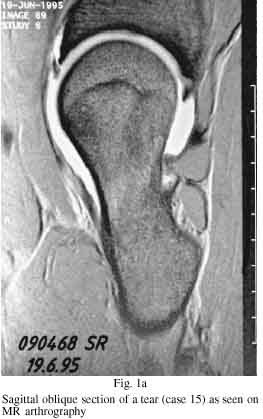

Since January 1993 we have carried out MR arthrography on 23 patients with

clinical symptoms and signs of abnormality of the acetabular labrum. Most of the

patients were young adults. Such symptoms are known precursors of

osteoarthritis, and therefore early and accurate evaluation is required. We

assessed the value of MR arthrography of the hip as a minimally-invasive

diagnostic technique, in a prospective study and compared the findings with

those at subsequent operations. All the patients complained of groin pain; 22

had a positive acetabular impingement test and 15 had radiological evidence of

hip dysplasia. In 21 of the patients, MR arthrography suggested either

degeneration or a tear of the labrum or both. These findings were confirmed at

operation in 18 patients, but there was no abnormality of the labrum in the

other three. In two of the patients, MR arthrography erroneously suggested an

intact labrum. Both MR arthrography and intraoperative inspection located

lesions of the superior labrum most often, and these appeared slightly larger on

arthrography than at operation. We consider that MR arthrography is a promising

diagnostic technique for the evaluation of abnormalities of the acetabular

labrum.